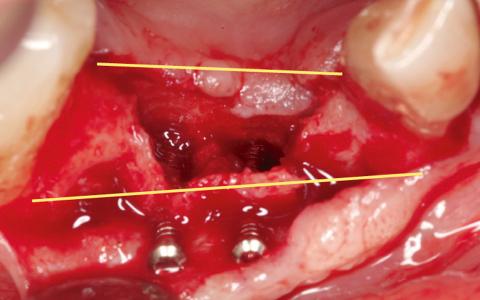

Paciente de 55 años al que le realizaron la extracción de los dientes 4.2- 4.2 con quistes apicales y bolsas superiores a 9 mm, con abscesos recurrentes. En la exploración clínica se observó una pérdida de tejido queratinizado y un defecto transversal. Se decide hacer un IGL para tener un buen tejido y así poder proteger el injerto.

Plan de tratamiento: Expansión y regeneración diferida.